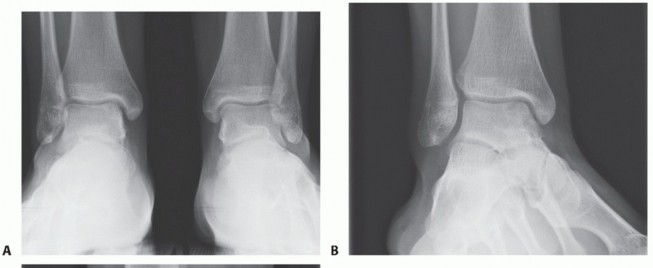

DEFINITION Lateral ankle sprains are the most common injury in sports, accounting for 15% to 20% of all athle…

DEFINITION Lateral ligament instability occurs in some patients after an inversion injury. 38 Although an inv…

DEFINITION Lateral ligament injuries of the ankle are treated conservatively with good results in most cases.…